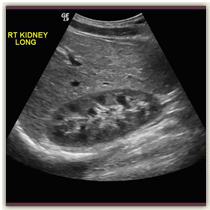

At Prohealth Advanced Imaging we perform many different types of ultrasound procedures. Some of these include evaluation of the abdomen, including the gallbladder, liver, kidneys, pancreas, spleen, and appendix; the pelvis, including uterus and ovaries; thyroid; scrotum and some pediatric imaging.

Ultrasound imaging, also known as sonography, is a safe and painless radiology imaging study. Ultrasound utilizes high frequency sound waves, without radiation, to generate images of the internal structures of the body. The reflected sound wave echoes are recorded and displayed as a real-time visual image. Because ultrasound images are captured in real-time, they can show movement of internal tissues and organs, and enable our Radiologists to see blood flow.

- Examining many of the body’s internal organs, including the liver, gallbladder, spleen, pancreas, kidneys, bladder, uterus, and ovaries.